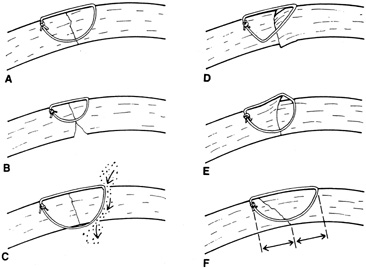

A number of options are available for suturing a corneal laceration. Tissue margins should appose as precisely as possible while suturing. The simplest method is to progressively halve the wound with simple interrupted sutures. Corneal sutures should be approximately 90% to 95% depth through the stroma, 1.5 mm in length, and of equal depth on each side of the wound. Shallow sutures create internal wound gape, whereas sutures of unequal length and depth on each side of the wound result in wound override. Sutures should generally not be passed through 100% thickness because the tract may theoretically act as a conduit allowing microorganisms from the external surface to enter the eye. For shelved lacerations, sutures should be placed equidistant with respect to the internal aspect of the wound and tied with minimal tension to achieve good tissue apposition, avoiding wound slippage with consequent tissue override (Fig. 5). Wounds with edematous or irregular margins generally require longer sutures for closure.